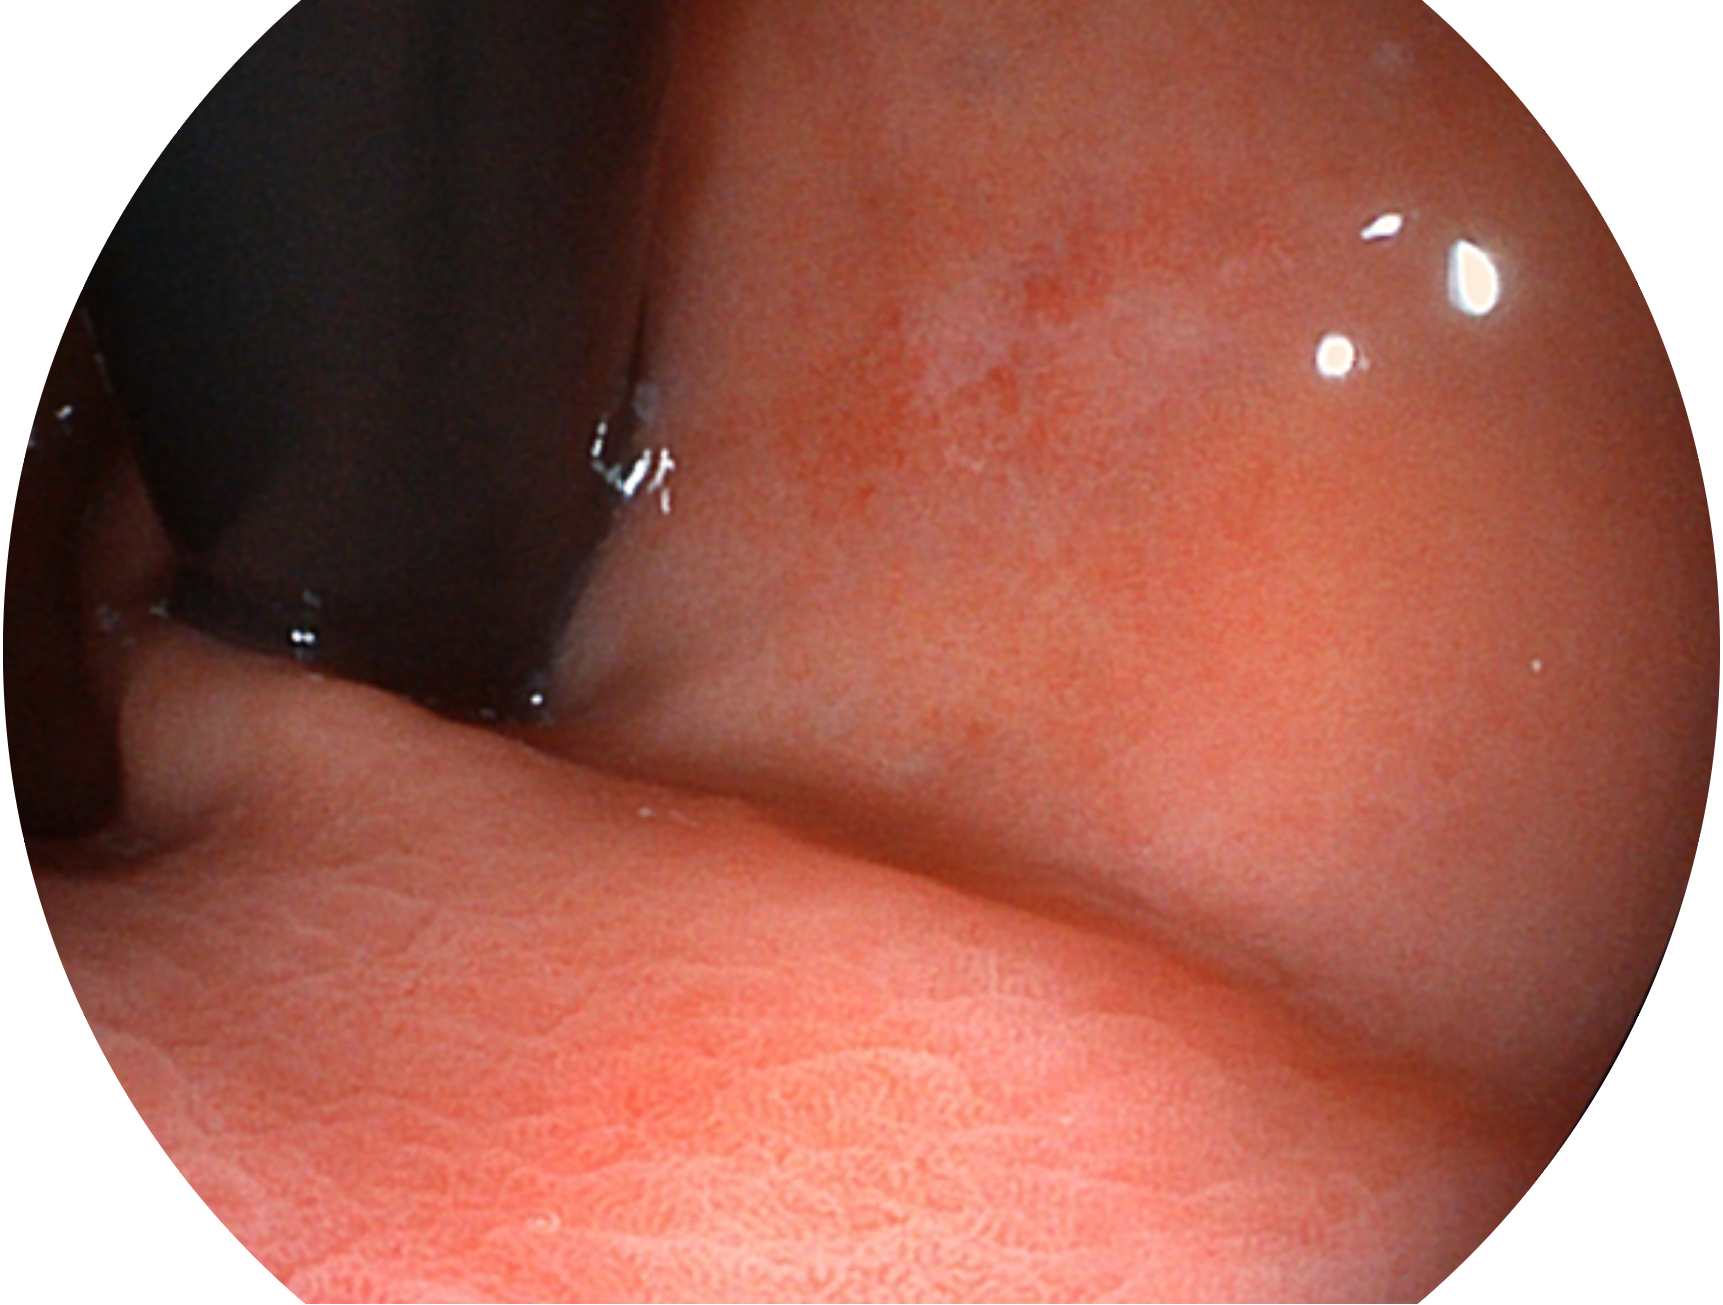

九州酷游新开发的内镜染色技术,主要是基于多波长LED 光源的开发,VLS-55Q 四波长LED 光源是由四个不同颜色的LED光按照相应照明模式所规定的特定发光比例进行合束后形成,合束后形成的照明光的光谱由红光、绿光、蓝光及蓝紫光这四个不同的波段范围构成。具有更高光谱自由度,通过光谱比例的控制,实现了聚谱成像技术,英文全称为“Spectral Focused Imaging, SFI”,缩写为“SFI”和光电复合染色成像技术,英文全称为“Versatile Intelligent Staining Technology, VIST”,缩写为“VIST”。